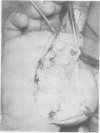

Pressure gun injection injuries are becoming increasingly common. Their effect on the fingers and hands, especially when improperly managed, can be devastating. Therefore it is important to review features, clinical course, anatomic distribution and operative management of such injuries. If a useful hand and fingers are to be attained, rapid and thorough decompression and debridement of these injuries are essential.